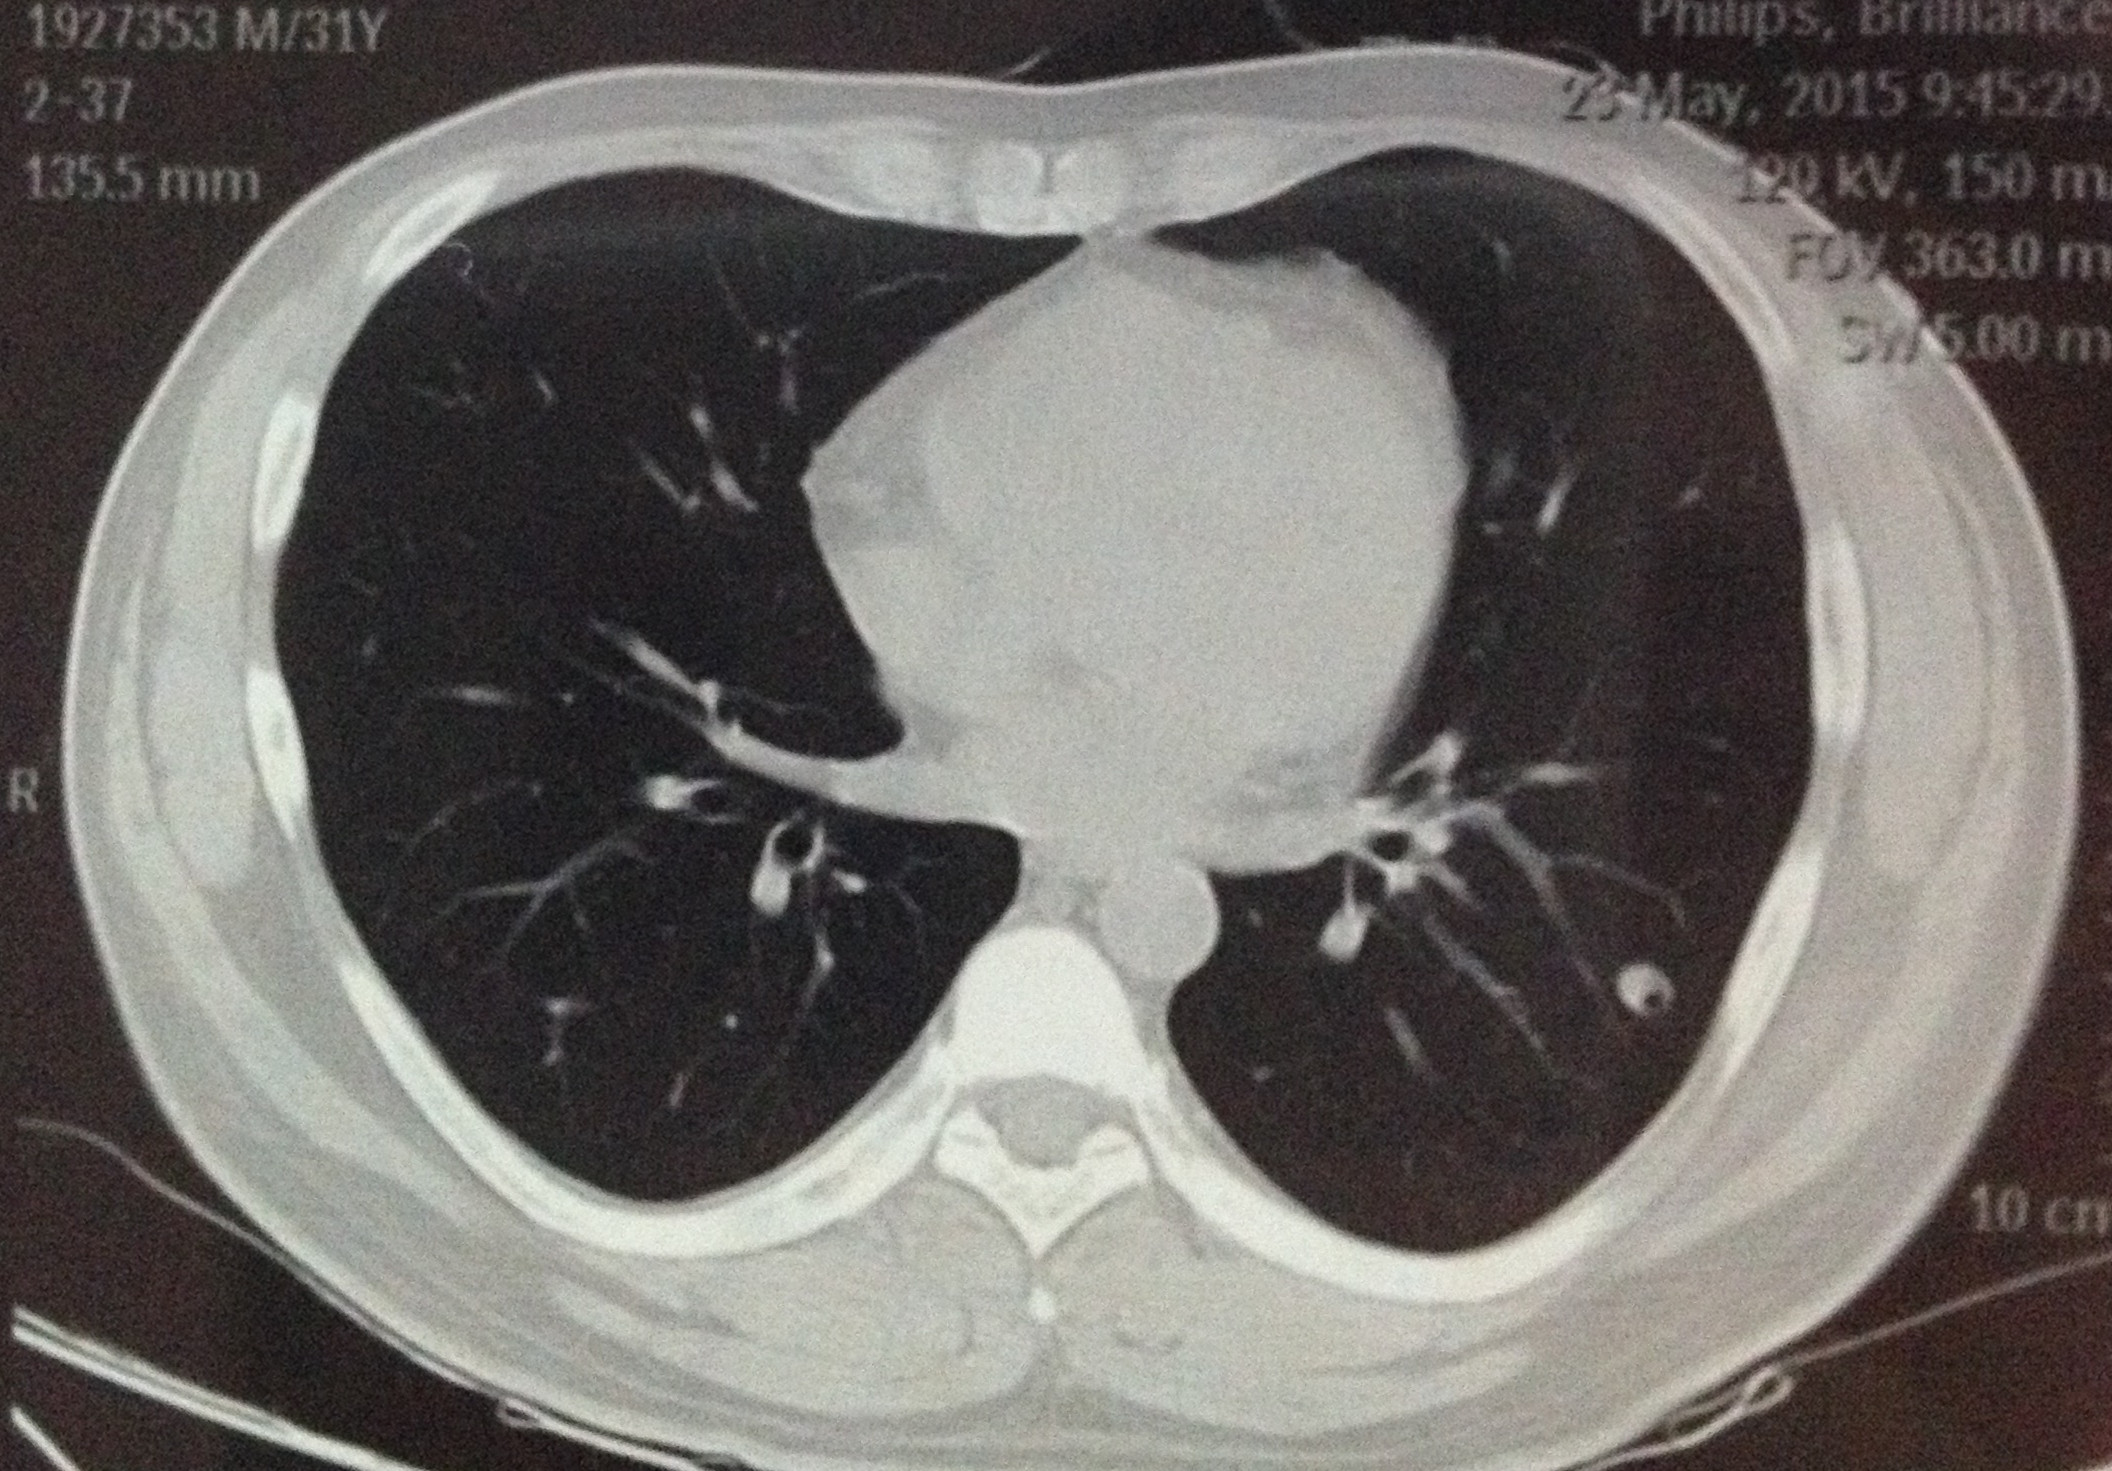

CT50519:偶然体检发现,三个月后显示空洞

三个月后复查,大小没有变化9mm*9mm,但是扫出来多了小空洞 原来诊断说是良性,错构瘤或者炎性假瘤或者结核球 这次医生不说是什么了,求各位专家给个意见 ...

良性结节可能性大,建议随诊、复查

良性结节可能性大,建议随诊、复查。

仍然考虑良性结节

建议薄层观察,仍然考虑良性结节可能性大